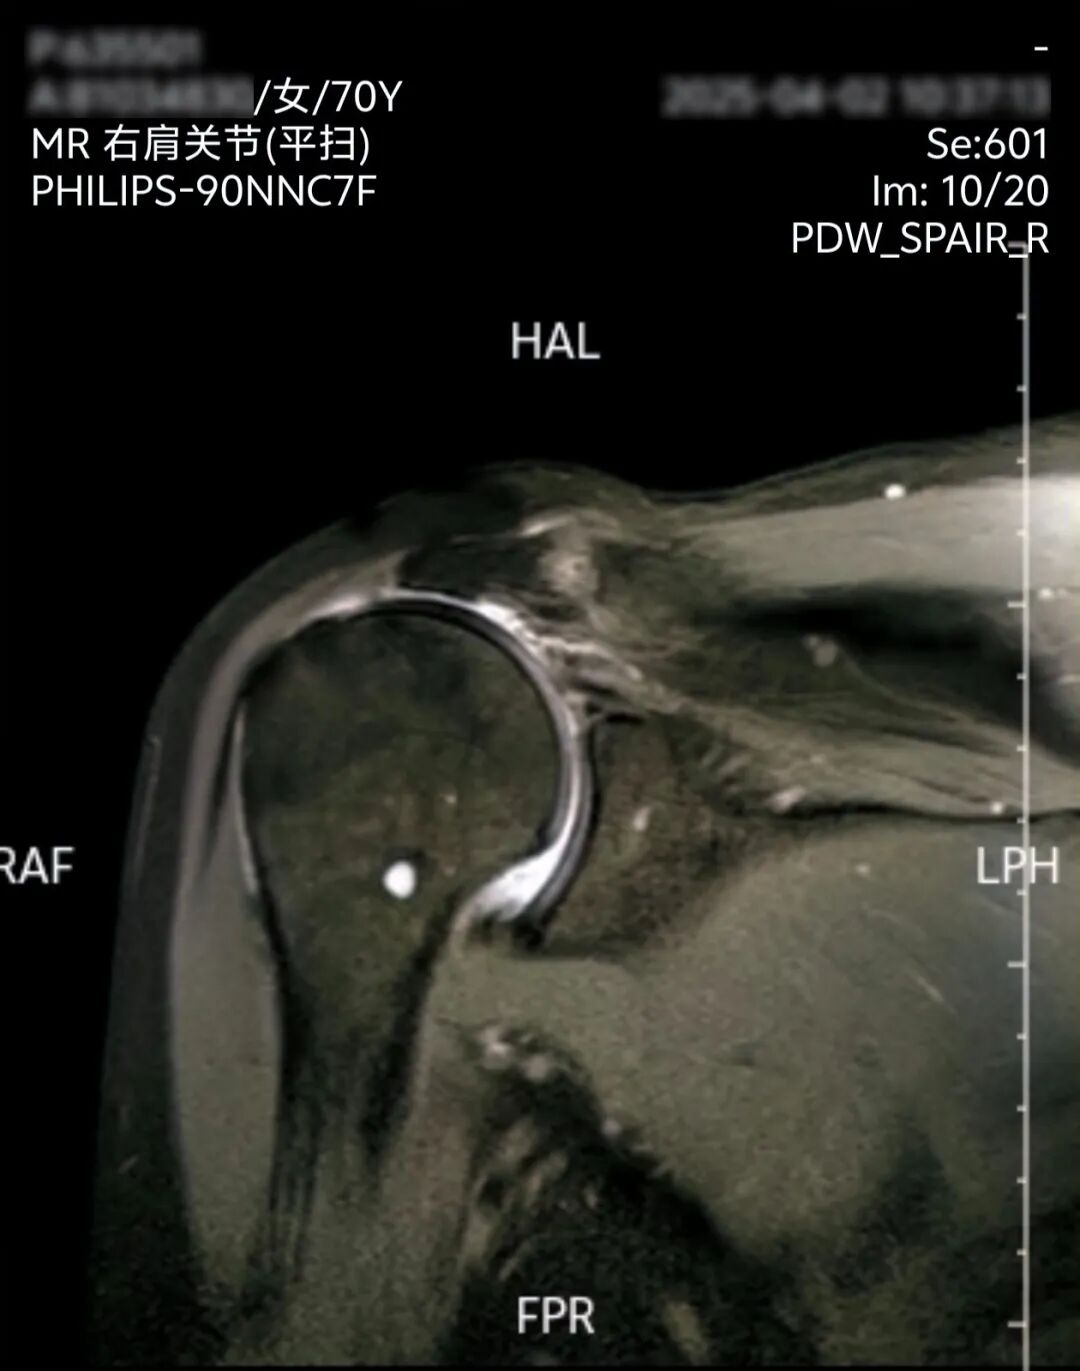

术前检查显示,该患者的肩袖严重萎缩,肱骨头上顶肩峰。